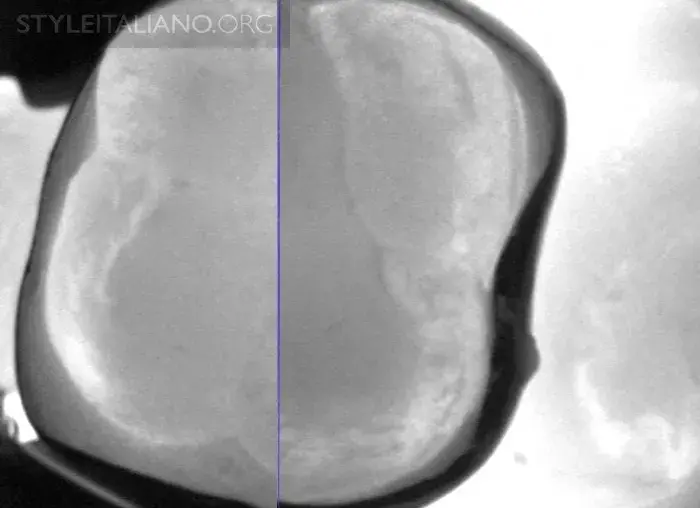

Трещина зуба на снимке

Рис. 30 — Трещина зуба на снимке.

Рис. 31 — Несколько трещин.

Рис. 32 — Вид поражения под трещиной.

Рис. 33 – Несколько трещин вблизи амальгамы.

Рис. 34 – Несколько трещин вблизи композитной реставрации.